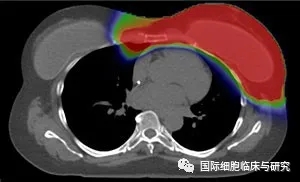

图片依次为质子治疗和常规X射线疗法

注:红色:高辐射剂量;绿色:中间辐射剂量;蓝色:低辐射剂量